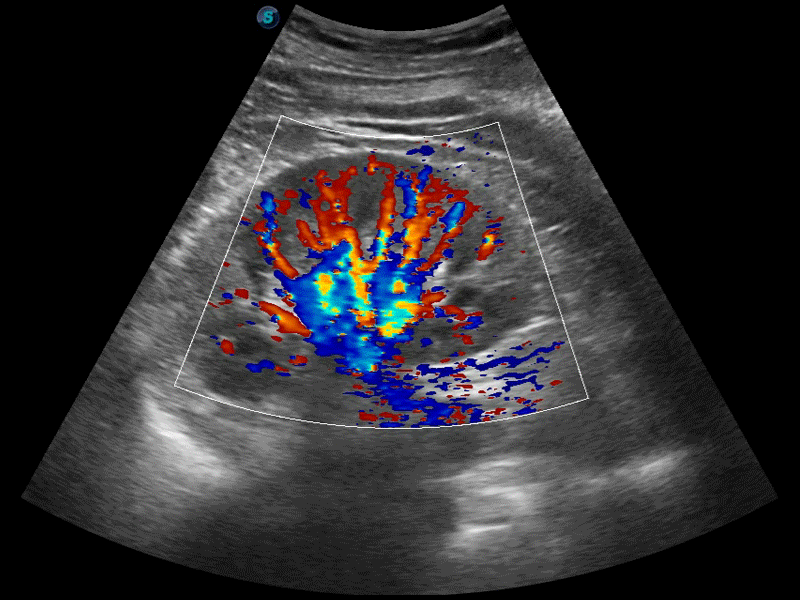

高分辨率血流成像技術提高了對低速血流信號的檢測能力。在提高空間分辨率的同時,也克服了血流外溢現象,為用戶提供更加真實的血流動力學信息。